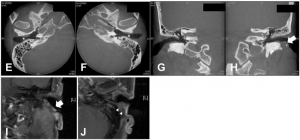

There were no invasive mass lesions in the external ear canal, but microcalcifications were found in the left ear canal, which is where the subcutaneous mass was placed on computed tomography (CT) pictures and the same could be seen in magnetic resonance imaging (MRI) data with enhanced quality of structures.

Fig. 2: CT scan images show bilateral external ear canal stenosis without accompanying bony destruction